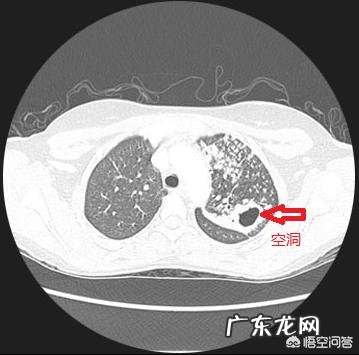

肺结核是一种叫结核分枝杆菌的病菌引起的慢性肺部感染性疾 , 痰里有结核杆菌的肺结核才会传染 , 痰里没有结核杆菌的肺结核是不会传染的 。痰里有结核杆菌的肺结核患者通过咳嗽、喷嚏、讲话等途径把含有结核杆菌的飞沫传播到空气 , 别人吸入到这些空气就有可能被感染 。要想知道痰里有没有结核杆菌 , 留取痰液送去做涂片检查或者痰培养检查就能监测出来了 。

什么是肺结核钙化?1.首先我们要明确 , 肺结核钙化了 , 代表的就是肺结核趋近于痊愈了 。肺结核是属于一种比较严重的疾病,如果自己身体素质相对较好,平时注意肺部保护的话,可能会使肺结核自己钙化 。但这种可能性相对来说比较小,因为一旦出现了肺结核的症状,一般肺部功能已经开始减弱,在平时即使注意保护,也不会有太大的功效 。

2.而如果是已经定期去医院进行检查和治疗的话,结核钙化就是指已经基本痊愈,可以出院,不需要再接受治疗了,因为肺结核在钙化了之后,就不会再出现其他的异常现象,肺部可以正常使用 。